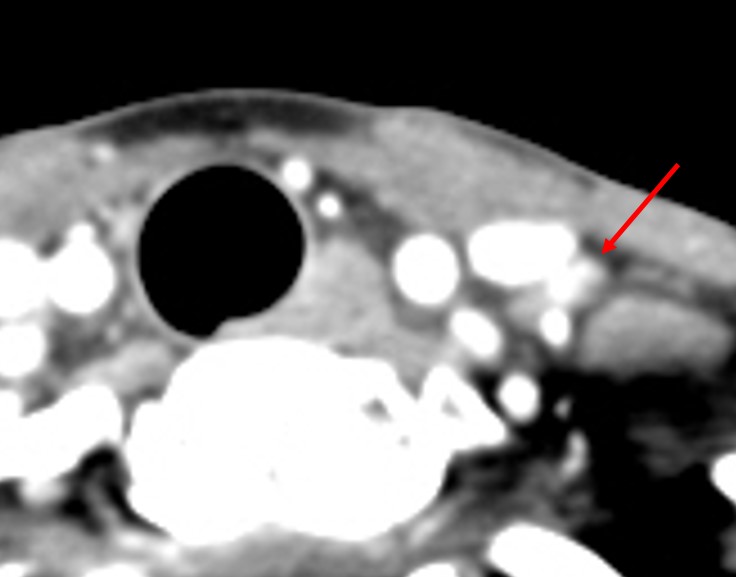

[353,] 42/F,검강검진상 발견된 갑상선 병변

Modality

US,CT,

Sae Rom Chung

,2025-10-25

진단은?

[Diagnosis]

Diffuse sclerosing subtype of PTC